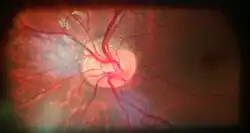

![]() Ophthalmoscopy photograph showing the optic disc as a bright area on the right where blood vessels converge. | |

The optic disc or optic nerve head is the point of exit for ganglion cell axons leaving the eye. Because there are no rods or cones overlying the optic disc, it corresponds to a small blind spot in each eye.

The ganglion cell axons form the optic nerve after they leave the eye. The optic disc represents the beginning of the optic nerve and is the point where the axons of retinal ganglion cells come together. The optic disc in a normal human eye carries 1–1.2 million afferent nerve fibers from the eye toward the brain. The optic disc is also the entry point for the major arteries that supply the retina with blood, and the exit point for the veins from the retina.[1]

Almost all eye structures can be examined with appropriate optical equipment and lenses. Using a modern direct ophthalmoscope gives a view of the optic disc using the principle of reversibility of light. A slit lamp biomicroscopic examination along with an appropriate aspheric focusing lens (+66D, +78D or +90D) is required for a detailed stereoscopic view of the optic disc and structures inside the eye.

A biomicroscopic exam can indicate the health of the optic nerve. In particular, the eye care physician notes the colour, cupping size (as a cup-to-disc ratio), sharpness of edge, swelling, hemorrhages, notching in the optic disc and any other unusual anomalies. It is useful for finding evidence corroborating the diagnosis of glaucoma and other optic neuropathies, optic neuritis, anterior ischemic optic neuropathy or papilledema (i.e. optic disc swelling produced by raised intracranial pressure), and optic disc drusen.